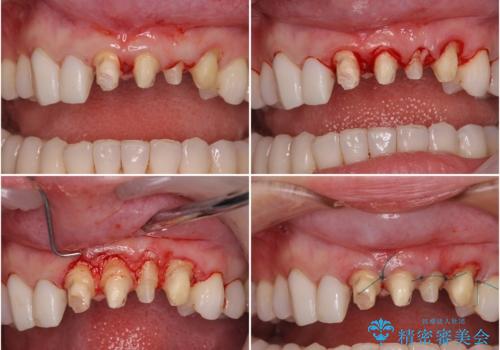

- 全体的なデコボコと、奥歯の欠損を放置した結果倒れ込んだ奥歯などを気にして来院された患者様です。

ワイヤー矯正の方が理想的な仕上がりとできる状態でしたが、上顎前歯にクラウンが装着されているため、インビザラインにて矯正治療を行うこととしました。

インビザラインのみで対応できないときにはワイヤー矯正を併用することとし、矯正治療後にはオールセラミッククラウンによる補綴治療を行うこととしました。

前歯は根管治療が必要となり、元々舌側に入り込んでいた左上2番目の歯は歯周外科処置により歯肉ラインを整えることとしました。